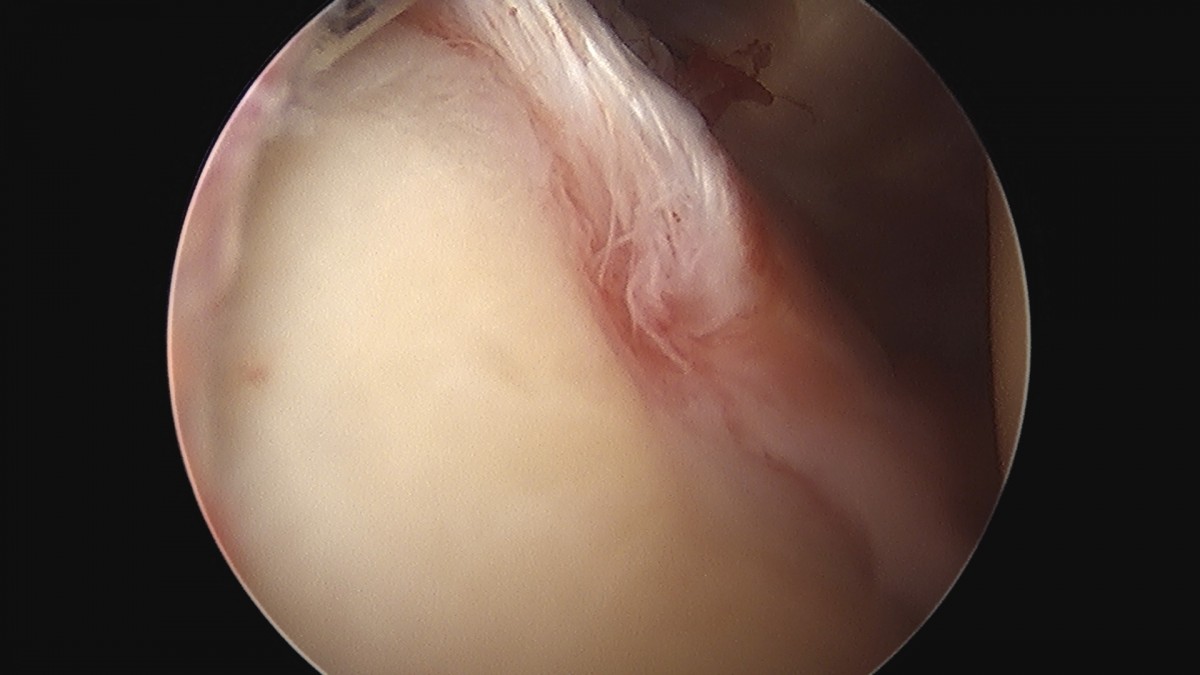

이재상원장님 어깨 견봉하 감압술 김선O 환자

작성자 최고관리자 댓글 0건 조회 823회 작성일 25-09-16 15:27